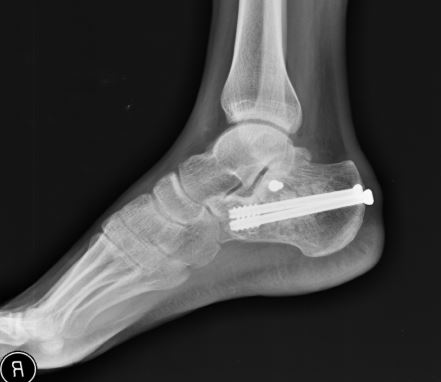

Surgery to repair a calcaneus fracture can restore the normal shape of the bone but is sometimes associated with complications such as wound healing problems infection and nerve damage. He was trimming branches on a ladder. After six weeks of rest it.

Non-surgically treated calcaneus fractures can develop many problems including. Treatment of these fractures may require surgery. Jan 29 2015 - Calcaneus fractures are severe injuries that can produce lifelong problems.

A displaced intra-articular calcaneal fracture DIACF is known for having a negative influence on the daily activities of patients. I had hoped that a stress fracture was somewhat better than PF because I could get healed and get back out there running but 2 weeks of not even being able to go for walks is really challenging me. For good calcaneus fracture recovery one must take considerable care of the heel bone and not place any weight on it for approximately 10 weeks after surgery.

I was non-weight bearing on the foot for about 8 weeks and walking again after 13 weeks. I have had the identical symptoms. I had a plate and 10 screws put in.

Unstable calcaneus fractures require surgery in order to properly heal. Most calcaneus fractures are closed injuries meaning the skin is intact. After calcaneus life reddit.

Saw an ortho surgeon who put me in a thermoformed cast then an air boot for a while and finally a. Complete calcaneus fracture recovery may take up to a year.